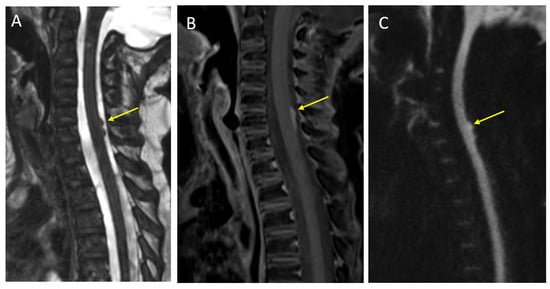

- Hayes, L.L.; Jones, R.A.; Palasis, S.; Aguilera, D.; Porter, D.A. Drop metastases to the pediatric spine revealed with diffusion-weighted MR imaging. Pediatr. Radiol. 2012, 42, 1009–1013. [Google Scholar] [CrossRef]

- Buch, K.; Caruso, P.; Ebb, D.; Rincon, S. Balanced Steady-State Free Precession Sequence (CISS/FIESTA/3D Driven Equilibrium Radiofrequency Reset Pulse) Increases the Diagnostic Yield for Spinal Drop Metastases in Children with Brain Tumors. AJNR Am. J. Neuroradiol. 2018, 39, 1355–1361. [Google Scholar] [CrossRef] [Green Version]